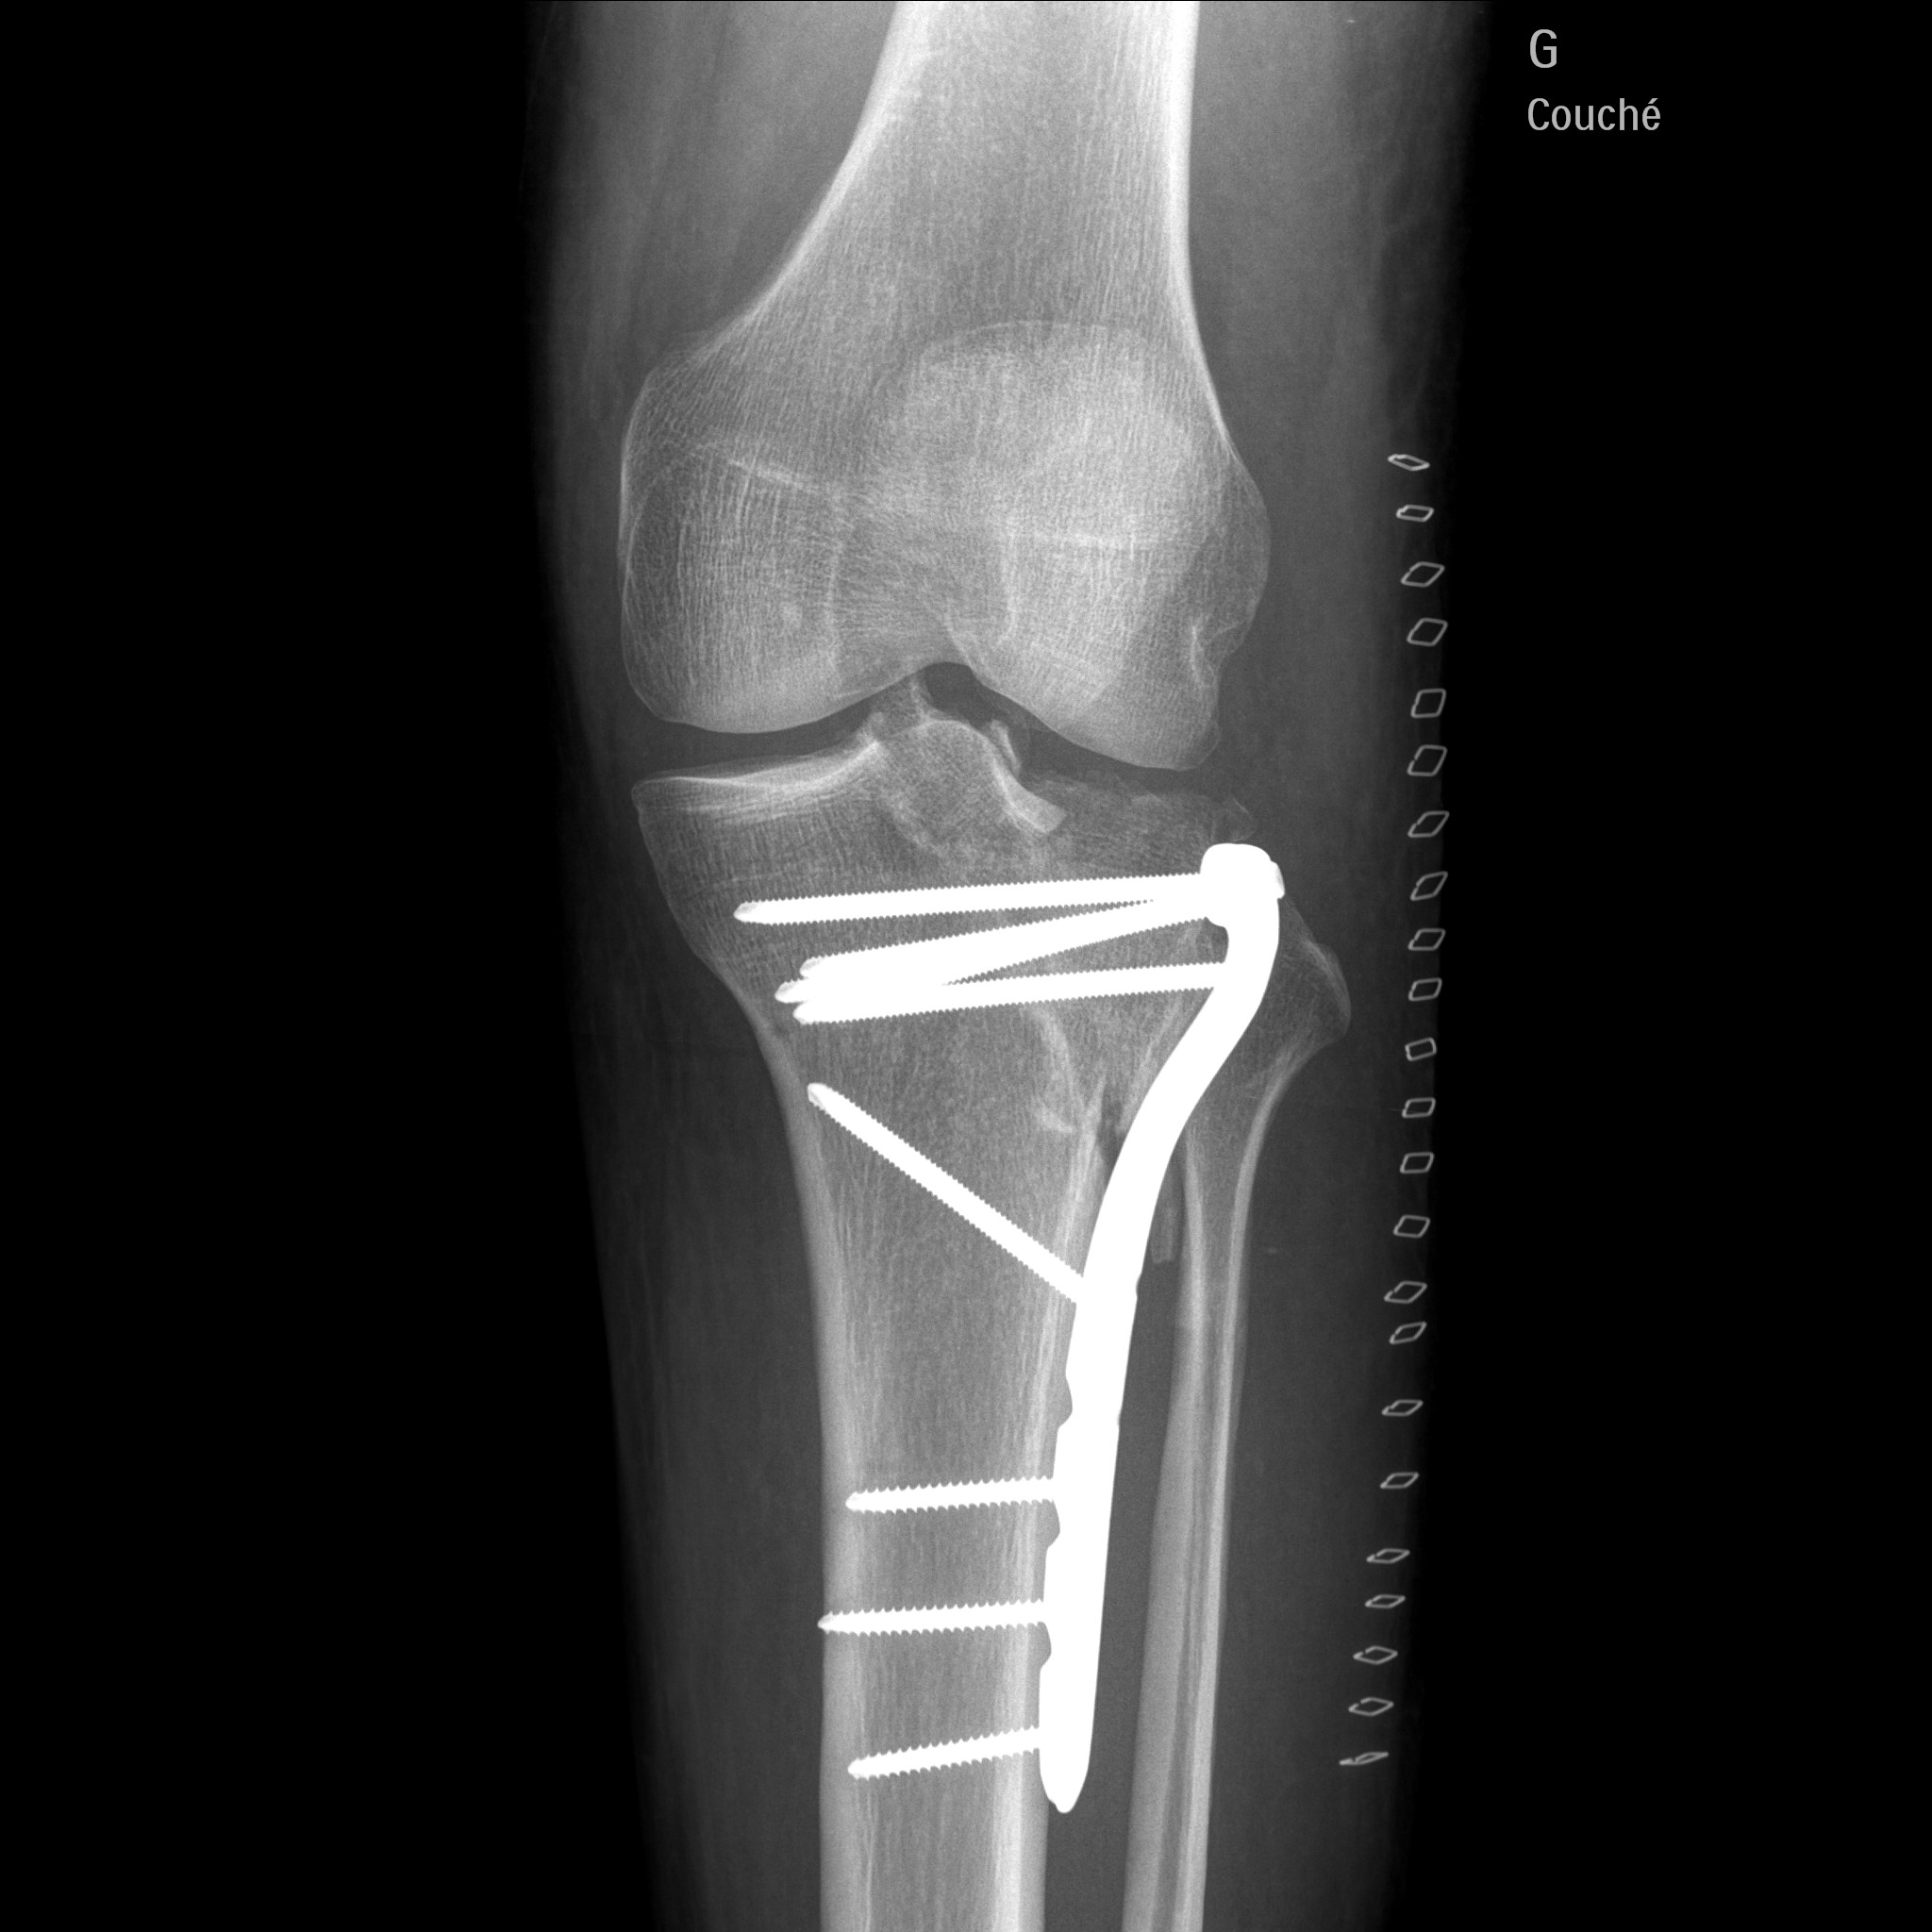

le tracteur est définitivement en pause

j'ai fait une sale chute en moto et j'ai du me faire opéré :( :( :( :(

j'en ai pour 3 mois sans pauser le pied a terre , et 6 mois de rééducation 1 an pour récupéré la totalité de ma jambes

1.3.46.670589.30.39.0.1.622692733605.1619697890621.1-f1.jpeg

Tu as dû avoir la trouille de ta vie. Un peu plus haut c'était toute l'articulation qui prenait.

J'ai énormément de chance de ne pas être mort

Je ferais un réglage donc je n'avais pas de casque

La moto en fin mobylette est coupé en deux

Voilà quand on fait le con

J'ai eu beaucoup de chance

Ouaouuu....ah oui c est du lourd la. Beau travail de chirurgie...a la hauteur de ce que tu sais faire de ton cote :wink: